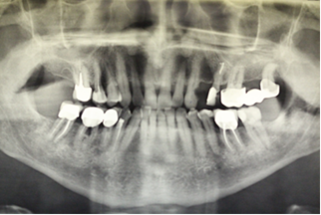

В основной группе 3 проводили фотодинамическую терапию с помощью препарата «Гелеофор» и светодиодного аппарата АФС «Спектр». По сравнению с традиционной антимикробной терапией с применением геля «Метрогил-Дента», противовоспалительный эффект которой наблюдался лишь после завершения всего курса лечения, пациенты группы 3 почувствовали улучшение своего состояния непосредственно на стоматологическом приеме после проведения фотодинамической терапии. После первого сеанса 24,0% пациентов отмечали снижение дискомфорта и болевых ощущений в полости рта, на которые жаловались до лечения. После второго сеанса ФДТ уже 62,0% пациентов субъективное улучшение. После третьего сеанса практически все пациенты (92,0%) отмечали улучшение состояния пародонта, снижение кровоточивости при чистке зубов, уменьшение воспаления десны и болевых ощущений. Улучшение состояния тканей пародонта подтверждалось и при объективном обследовании полости рта (Рисунок 14).

| Клиническая картина до лечения | Ортопантомограмма до лечения |

| Проведена профессиональная гигиена | Обработка ПК гелем «Гелеофор» |

| Активация фотосенсибилизатора | Состояние после первого сеанса ФДТ |

| Состояние после второго сеанса ФДТ | Состояние после третьего сеанса ФДТ |

| Рисунок 14. Динамика состояния тканей пародонта у пациента с ХГП тяжелой степени группы 3 в ходе проведения курса фотодинамической терапии. | |